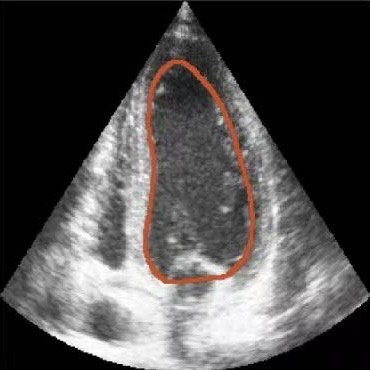

Figure 7: Visual comparison with state-of-the-art methods on the CAMUS test set. Green, red, and yellow regions represent the ground truth, prediction, and overlapping regions, respectively.

Visual comparison with SOTA. A visual comparison of GDKVM with other state-of-the-art methods is presented in Fig. 7, illustrating the ability of GDKVM to preserve structural integrity and delineate precise boundaries in difficult frames. Although prior approaches have significantly advanced heart cavity segmentation, they can still produce over-segmentation (including extraneous areas beyond the heart cavity) or under-segmentation (missing parts of the ventricle). In these challenging cases, existing methods sometimes deviate from the ground truth shape by forming gaps or protrusions. GDKVM, by contrast, adheres more closely to the anatomical contours, generating cleaner masks with noticeably fewer artifacts. This property yields higher segmentation fidelity on frames where earlier approaches often falter.